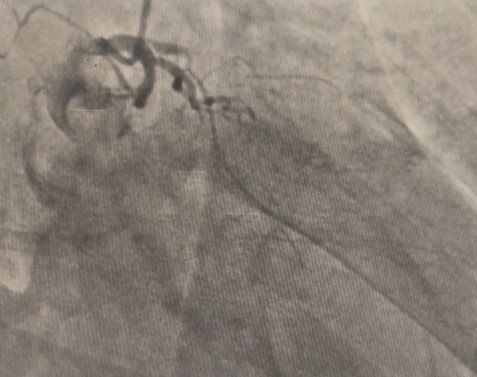

The LM had 50% ostial stenosis. LAD showed proximal CTO with bridging collaterals from the right coronary artery. LCx demonstrated proximal CTO with contralateral collaterals from the RCA. The right coronary artery was dominant with mild disease. The case represented complex dual CTO with LM involvement, posing both technical and procedural challenges due to tortuosity and calcification.

A dual access strategy was used: right radial for RCA and right femoral for LCA. For LCx CTO PCI, a Finecross microcatheter (Terumo, Japan) was advanced to the distal LCx. Predilation was done using a 2.5 ¡¿ 15 mm Firefighter balloon (Medtronic, USA) at 8 atm, followed by stenting with a 3.5 ¡¿ 30 mm Orsiro Mission drug-eluting stent (Biotronik, Germany) at 16 atm. Postdilation was performed with a 3.0 ¡¿ 15 mm Accuforce non-compliant (NC) balloon (Terumo, Japan) at 14 atm.For LAD CTO PCI, Finecross with Fielder wire (Asahi, Japan) failed to cross; Gaia First (Asahi, Japan) successfully reached the distal LAD. Predilation was performed using NC Sapphire 24 (OrbusNeich, Hong Kong) 3.5 ¡¿ 12 mm and Wedge NC (Boston Scientific, USA) 3.0 ¡¿ 15 mm. A 3.0 ¡¿ 40 mm Biofreedom Ultra stent (Biosensors, Singapore) was deployed at 14 atm. Proximal dissection into LM was noted, requiring LM–LAD stenting with 3.5 ¡¿ 22 mm Orsiro Mission and proximal optimization technique (POT) using 4.5 ¡¿ 18 mm NC Emerge balloon (Boston Scientific, USA). Intravascular ultrasound (IVUS) revealed ostial–proximal LCx disease, confirming a bifurcation lesion. Ostial LCx was predilated with a 3.5 ¡¿ 12 mm NC Sapphire balloon and stented with a 3.5 ¡¿ 14 mm Biofreedom Ultra. Final kissing balloon inflation was done with NC Sapphire 3.5 ¡¿ 12 mm (LAD) and 3.5 ¡¿ 14 mm (LCx), followed by final POT with NC Emerge 4.5 ¡¿ 8 mm balloon at 18 atm. Final shot revealed TIMI 3 flow with no dissection or perforation.